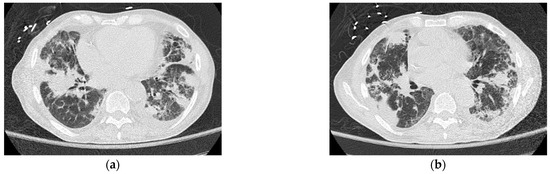

Further probing revealed that the patient’s history of pulmonary disorder was never treated nor investigated. Physical examination revealed abnormal skin hypopigmentation and oral leukoplakia. The patient’s radiographic studies showed scoliosis with advanced degenerative spondylosis and steatosis of the liver with diffuse hepatocellular changes despite having no history of alcoholism (Figure 3). Of note, family history was significant for the patient’s mother and sister dying of rapidly progressing fulminant PF in their 50 s.

Figure 3. Computerized tomography of the liver shows steatosis with diffuse hepatocellular change.